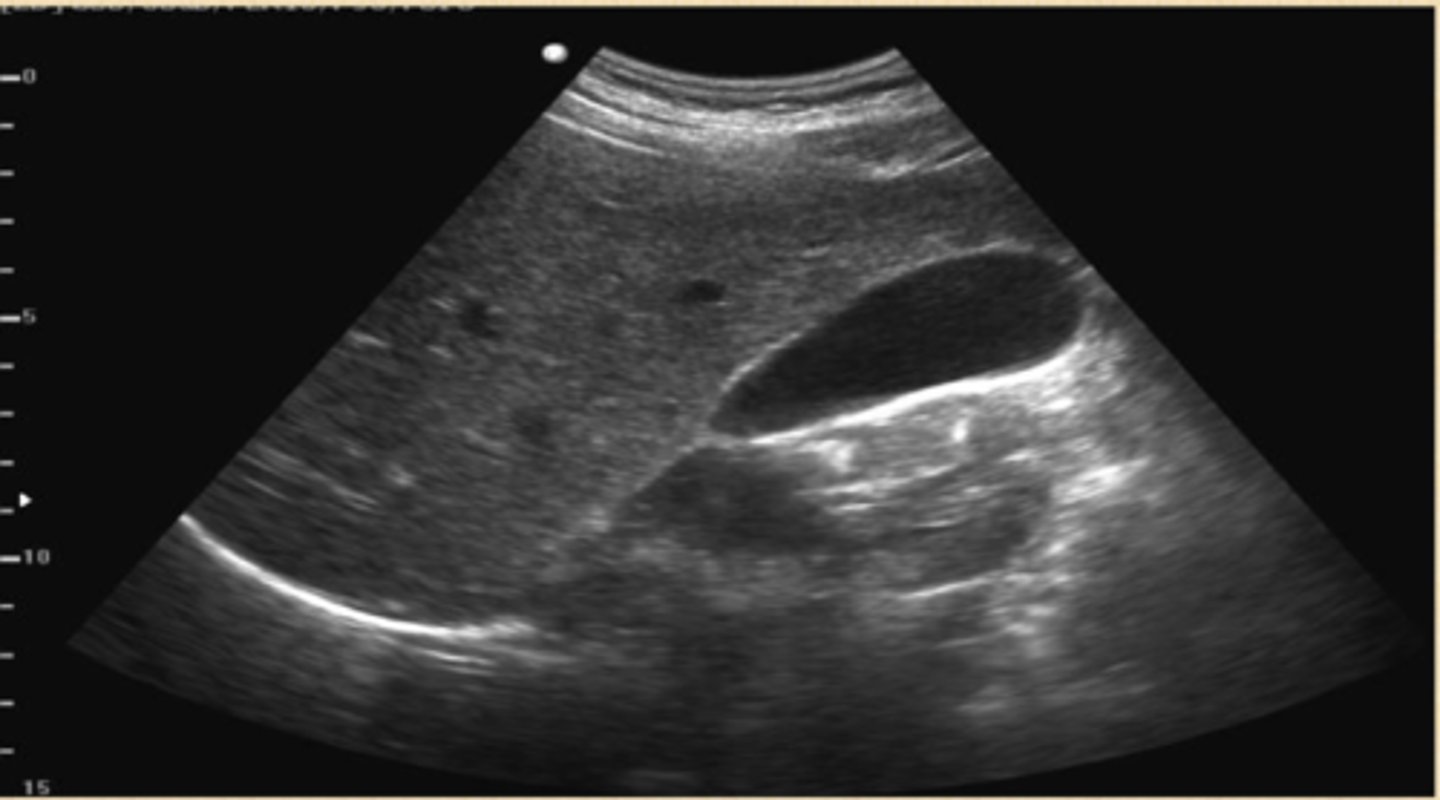

cholelithiasis

stones in the gallbladder, often asymptomatic, classic biliary pain characterized by infrequent episodes of steady severe pain in epigastrium or RUQ with radiation to R scapula

echogenic stones, posterior acoustic shadowing